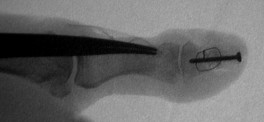

Exploration revealed no discrete  tumor, and a nondiagnostic frozen section. Because of diagnostic uncertainty and in order to avoid intraoperative cross contamination, a cancellous freeze dried allograft was used as a terminal graft:

This incorporated, with some terminal resorption: